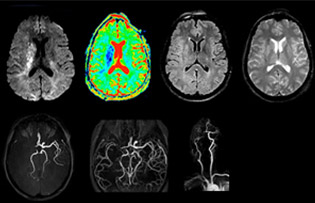

Every minute counts in stroke imaging

“In France, every stroke is usually imaged with MRI, not CT, even for emergency treatment.” “In France, stroke is usually imaged with MRI, not CT, even for emergency treatment. This is because MRI helps us directly visualize ischemia in the acute phase, but can also help rule out differentials such as MS and hematoma. In addition, we can assess the intracranial and extracranial vessels during the same examination,” says Dr. Savatovsky.

The first challenge in MRI of stroke is speed. The patient typically arrives from an ambulance in the MRI preparation room and the installation is done on a separate dock outside the scanner room. “The venous access is placed during the neurological examination. If the delay from the first symptoms allows the patient to receive thrombolysis we do a very fast examination that typically lasts about 11 minutes including the pre-scans. In the case of transient ischemic stroke we usually add ASL perfusion because in some symptoms with negative diffusion, ASL sometimes indicates a vascular origin.”

“Ingenia provides great flexibility in the parameters setting. We can tune a sequence the way we want,” says Dr. Savatovsky. “For example, in a stroke exam we use a FLAIR sequence of about two minutes instead of the four-minute FLAIR we use for MS. The diffusion is 30 seconds, the T2*-weighted scan is 30 seconds, the angiography scan time is less than one minute. Ingenia is a great scanner in that situation; even with these fast sequences we can achieve good images with good SNR. When the first sequence tells us that it’s not an ischemic stroke but a hemorrhagic stroke, we may switch to a time-resolved angiography to look for vascular malformations and venous thrombosis.

The ideal stroke protocol?

“Every center is different, but for me the ideal protocol for stroke includes diffusion weighted imaging, FLAIR, and fast susceptibility imaging,” says Dr. Savatovsky. “Our fast susceptibility weighted imaging takes 50 seconds, so it’s as fast as T2*-weighted imaging. It visualizes hemorrhage but also the clots. We also do 3D MR angiography that provides information on cervical and brain vessels. If the patient does not need immediate treatment, or if additional information is needed to decide on treatment, we might also add perfusion imaging and post-contrast T1-weighted imaging.”